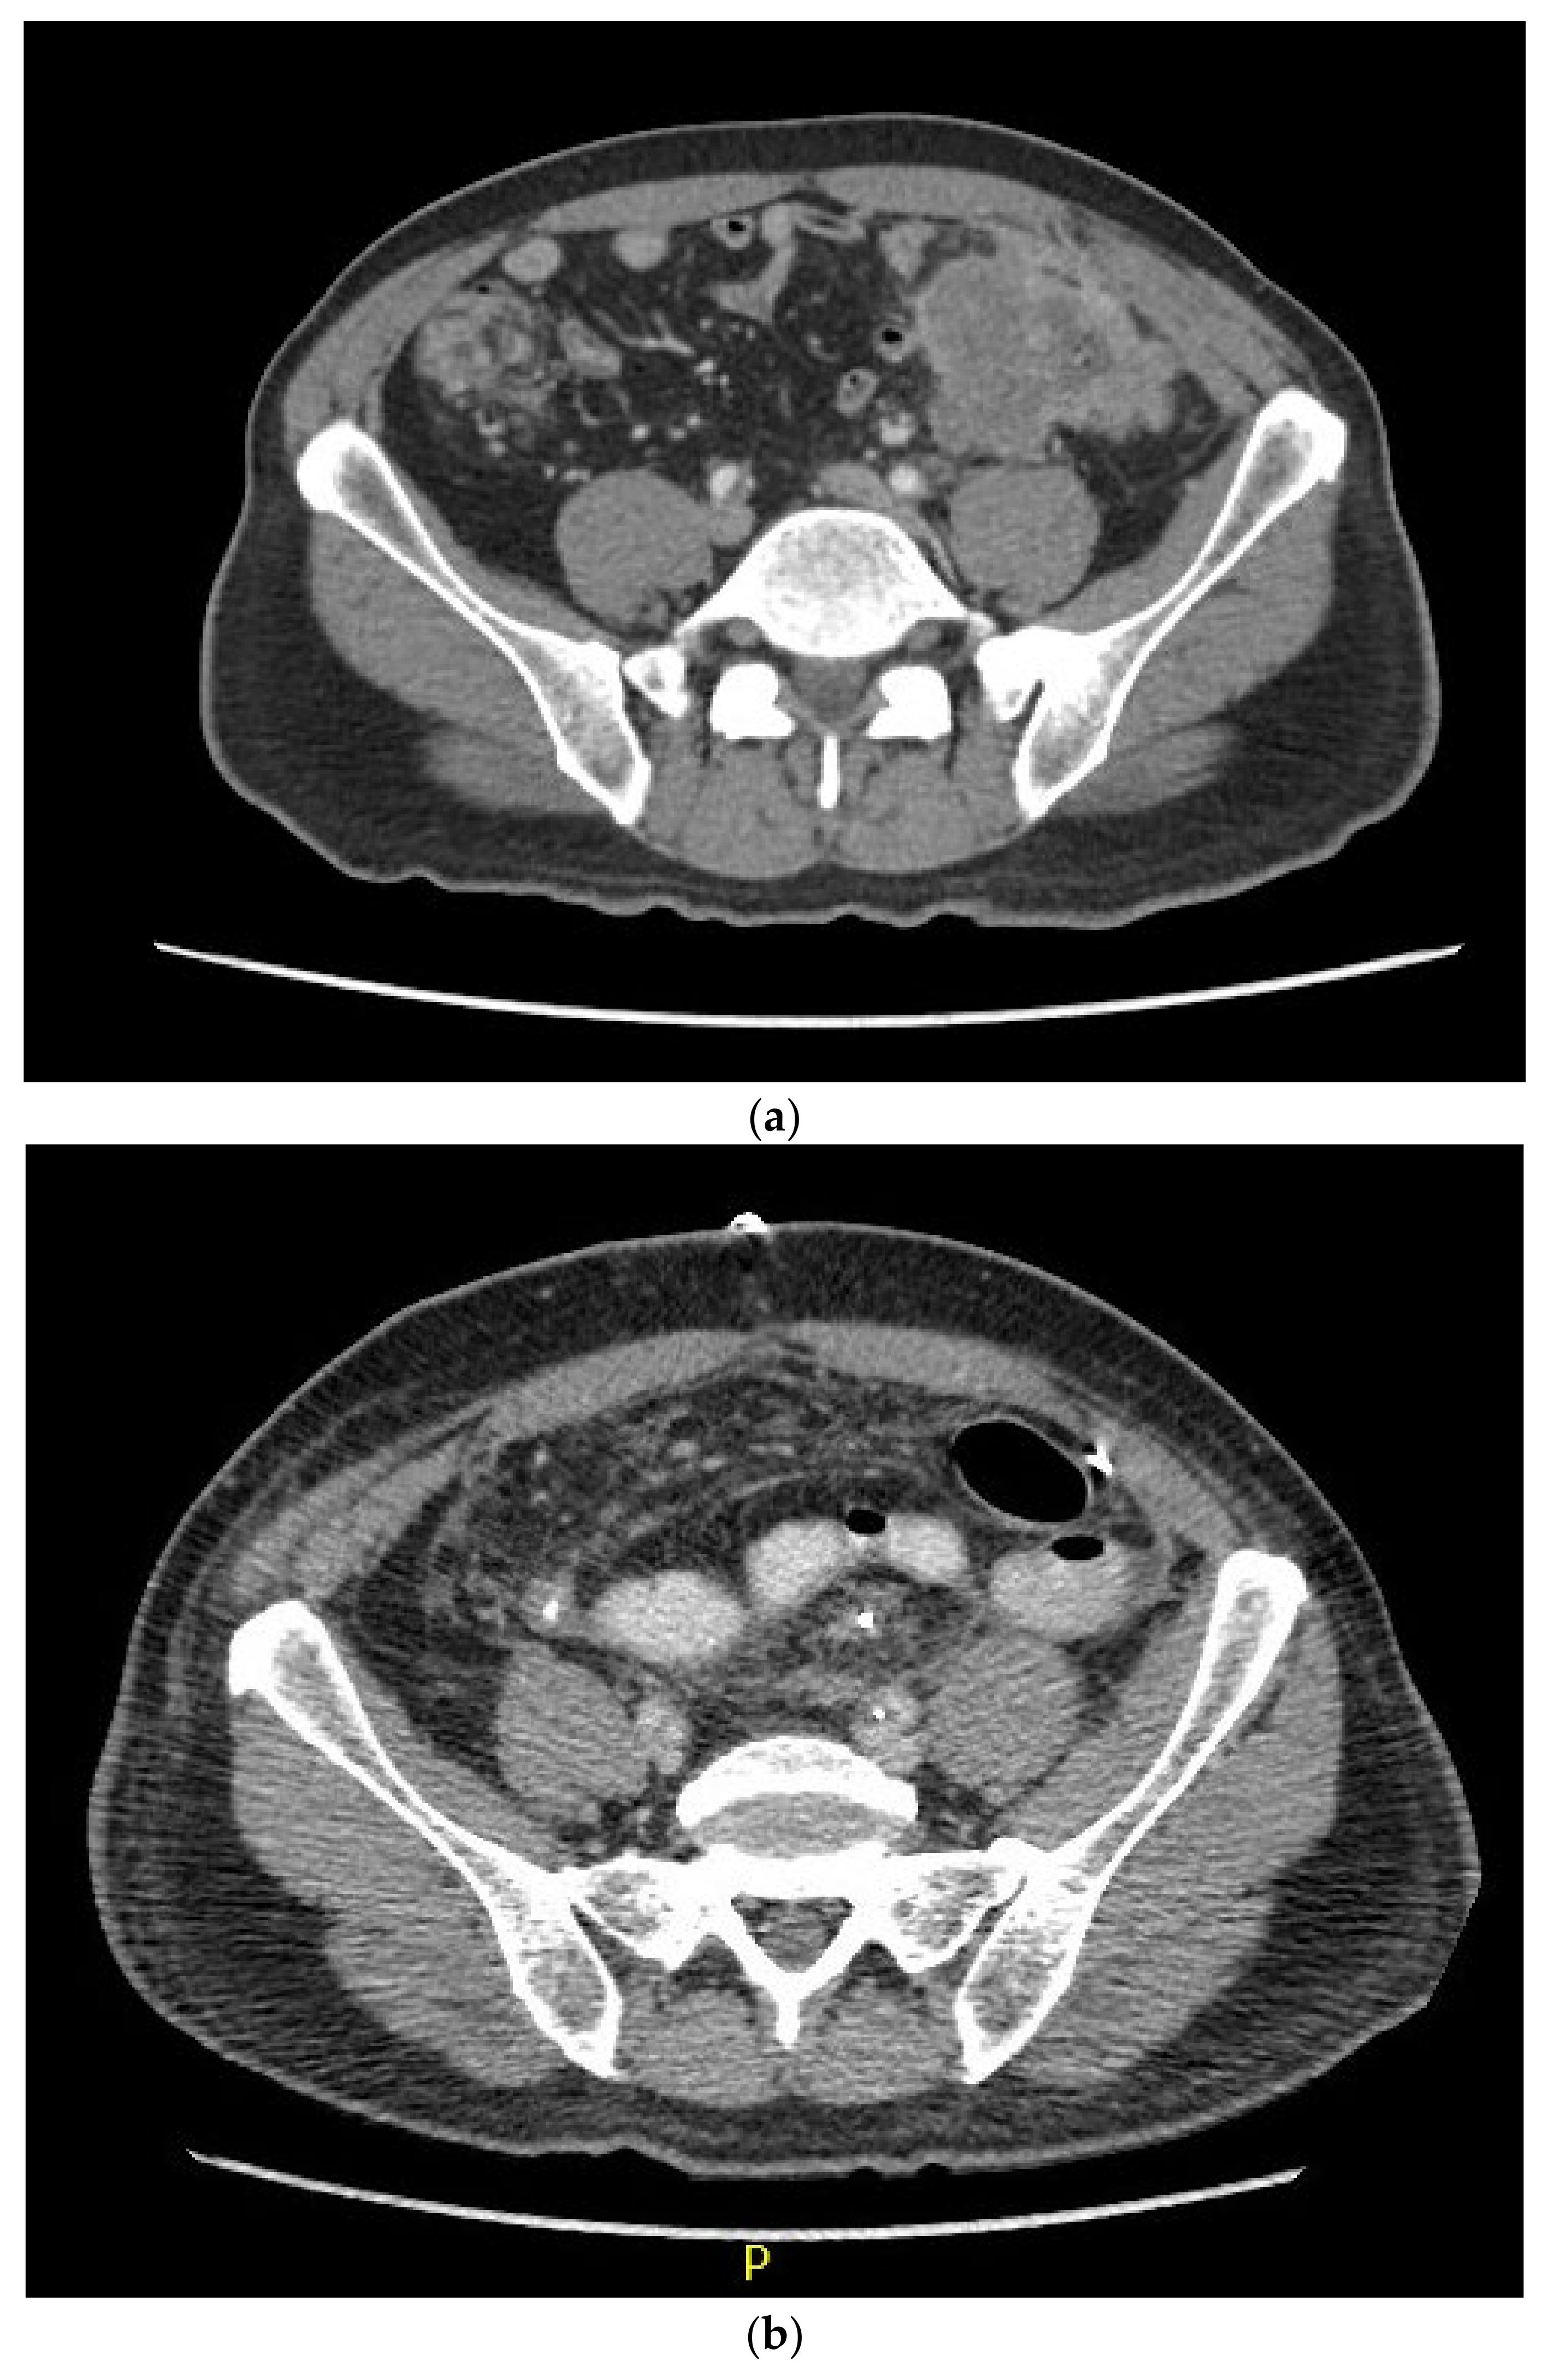

After six cycles of pembrolizumab, the patient’s tumours were no longer palpable on physical examination. Repeat CT scans in August 2021 (Figure 1) showed an interval decrease in the size of both tumours as well as the lymph nodes, potentially a complete response, although a commitment was not made at the time. At this point, the decision was made to attempt surgical resection, which allowed the patient to be taken to the operating theatre for total abdominal colectomy, en bloc resection of the left abdominal wall and left ureter, ileorectal anastomosis, cystoscopy with retrograde pyelogram and bilateral ureteric stent placement, and reconstruction of the left ureter with a Boari primary flap in October 2021. The patient tolerated this procedure well, without significant post-operative complications.

Figure 1.

CT scans from (a) February 2021, pre-treatment, and (b) October 2021, pre-surgery.